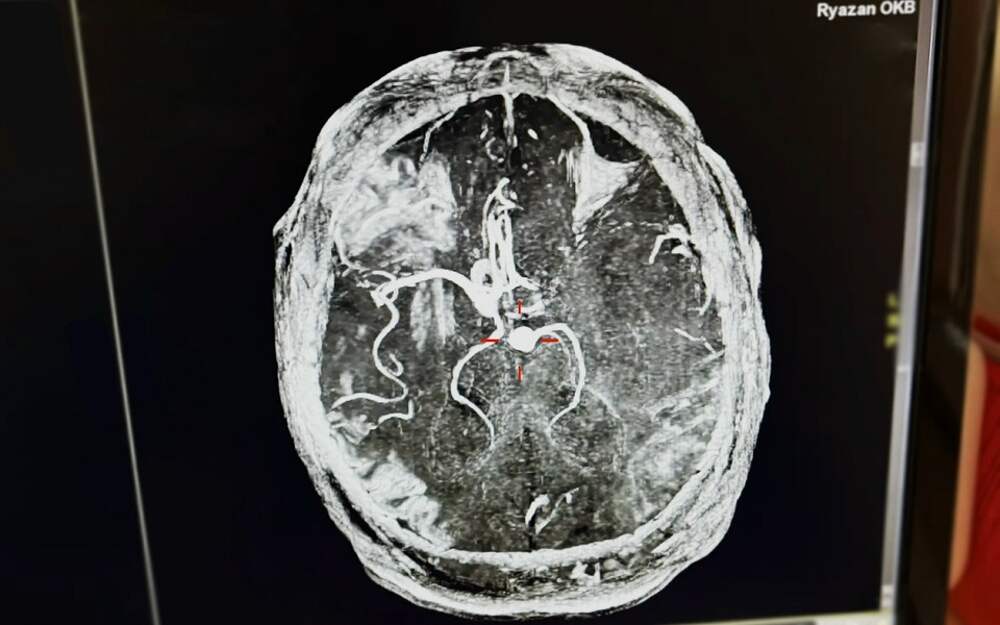

Пил по 8 банок энергетика: врачи чудом спасли 43-летнего рязанца с инсультом

Скорую помощь вызвала жена пациента - у него внезапно отнялась половина тела. Врачи оперативно доставили мужчину в ОКБ. "Ему измерили давление, и результаты оказались шокирующими — 265/155, что свидетельствовало об опасном гипертоническом кризе", - рассказали в минздраве. Диагностировали инсульт.